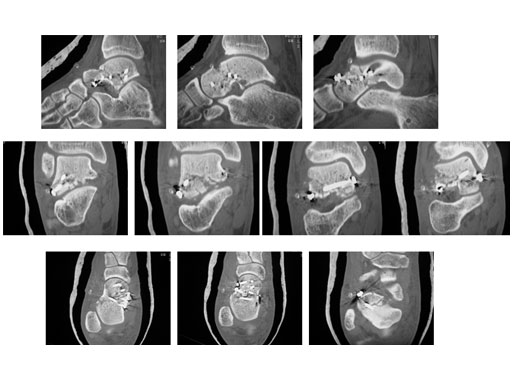

23-year-old male with moto cross accident

Case provided by P. Cronier, Angers, France

ORIF (day 5): Anteromedial approch and Ollier approach